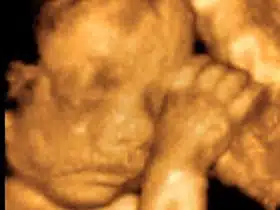

Trudnoća ili “drugo stanje” vrijeme je kada se u maternici majke razvija plod. Trudnoća se ...